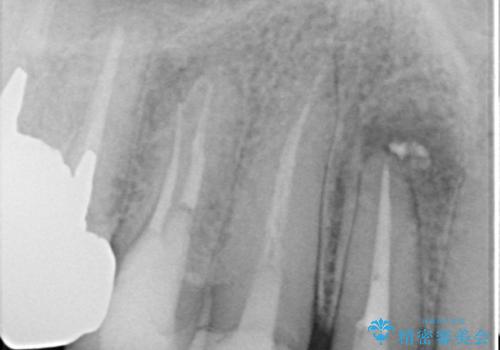

また、右上側切歯は根管治療が必要な状態でした。

右上側切歯に対して根管治療を行い、その後右上側切歯から左上犬歯まで計5本をオールセラミッククラウンで補綴する治療計画をご提案しました。